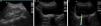

Renal colic is a common reason for presentation to emergency departments, and imaging has become fundamental for the diagnosis and clinical management of this condition. Ultrasonography and particularly noncontrast computed tomography have good diagnostic performance in diagnosing renal colic. Radiologic management will depend on the tools available at the center and on the characteristics of the patient. It is essential to use computed tomography techniques that minimize radiation and to use alternatives like ultrasonography in pregnant patients and children. In this article, we review the epidemiology, clinical and radiologic presentations, and clinical management of ureteral lithiasis.